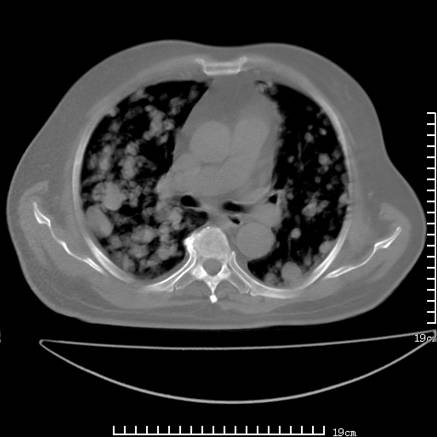

张男,75岁,干咳半年余,小便不利二年,b超检查前列腺增大,未见明显肿块;前列腺癌血生化检查多项指标明显增高。

双肺内多发转移瘤,纵膈淋巴结转移。来源前列腺?建议盆腔mri进一步检查。

双肺转移满了。

两肺广泛转移瘤。